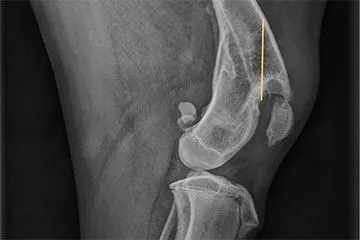

Lochen/Wien, 9.10.2020 - Kurz vor dem Welthundetag musste sich die Tierschutzorganisation Pfotenhilfe eines ganz speziellen Hundeschicksals annehmen: Dem erst knapp acht Monate alten Mischlingshund Maxi konnte vor wenigen Tagen durch eine spezielle Operation eine hoffnungsvolle Zukunft ermöglicht werden. Maxi musste vor Kurzem stark hinkend vom Tierschutzhof Pfotenhilfe im Salzburger Seengebiet aufgenommen werden. In der Tierklinik entdeckte man auf den Röntgenbildern eine unbehandelte, alte Fraktur, bei der sich ein Knochenzapfen gebildet hatte, der in das Knie des armen Tieres drückte. Dies verursachte dauerhaft höllische Schmerzen. Mittels einer aufwendigen Operation konnte dem jungen Rüden aber schnell geholfen werden.